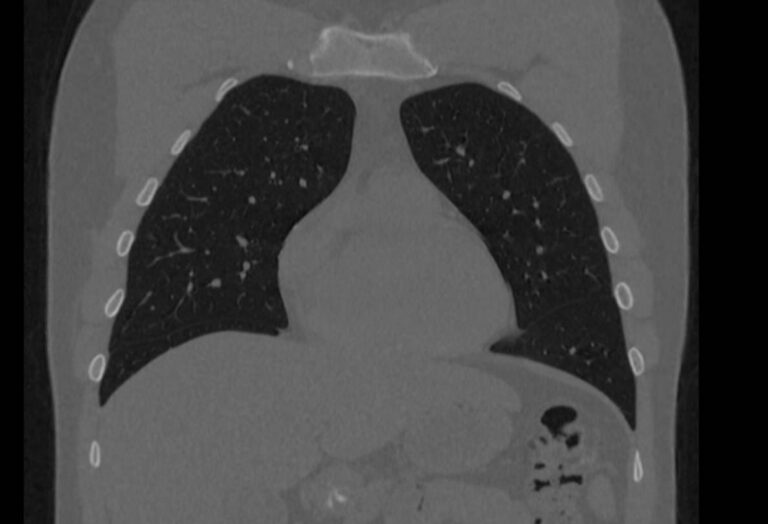

При проведении мультиспиральной компьютерной томографии на снимках и трехмерных изображениях хорошо видны костные структуры грудины, передней поверхности ребер, грудино-ключичных и грудино-реберных сочленений. Также можно увидеть строение и патологические процессы в органах средостения: трахеи, пищевода, лимфатических узлов средостения, вилочковой железы, загрудинно расположенной щитовидной железы, грудной аорты, сердца и перикарда, жировой клетчатки средостения.

С помощью мультиспиральной КТ грудины можно диагностировать: